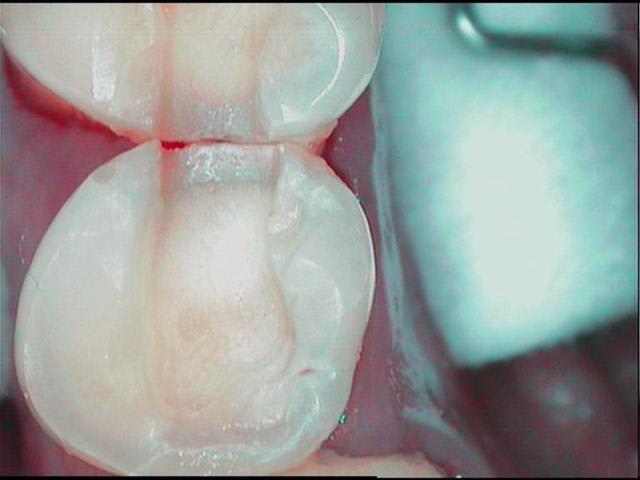

Initial abrasion vt1yph - Eugenol

j'ai eu un peu le meme genre de cas adressé, mais plus simple que le tien. j'étais un peu bridé pour le traitement a cause d'un bridge quasi complet en haut